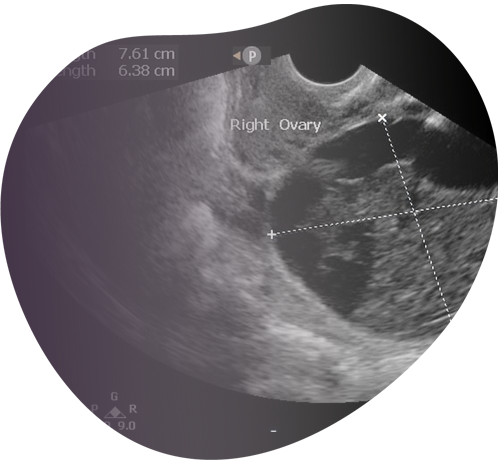

Ultrasonido Vaginal

Examen especializado que captura imágenes precisas del útero, ovarios y cuello uterino, útil para el seguimiento y/o el diagóstico.

Este estudio permite la visualización en detalle de los órganos reproductores y el desarrollo fetal, ofreciendo información valiosa para el diagnóstico, el seguimiento y la planificación del tratamiento.

Ultrasonido Gineco-Obstétrico